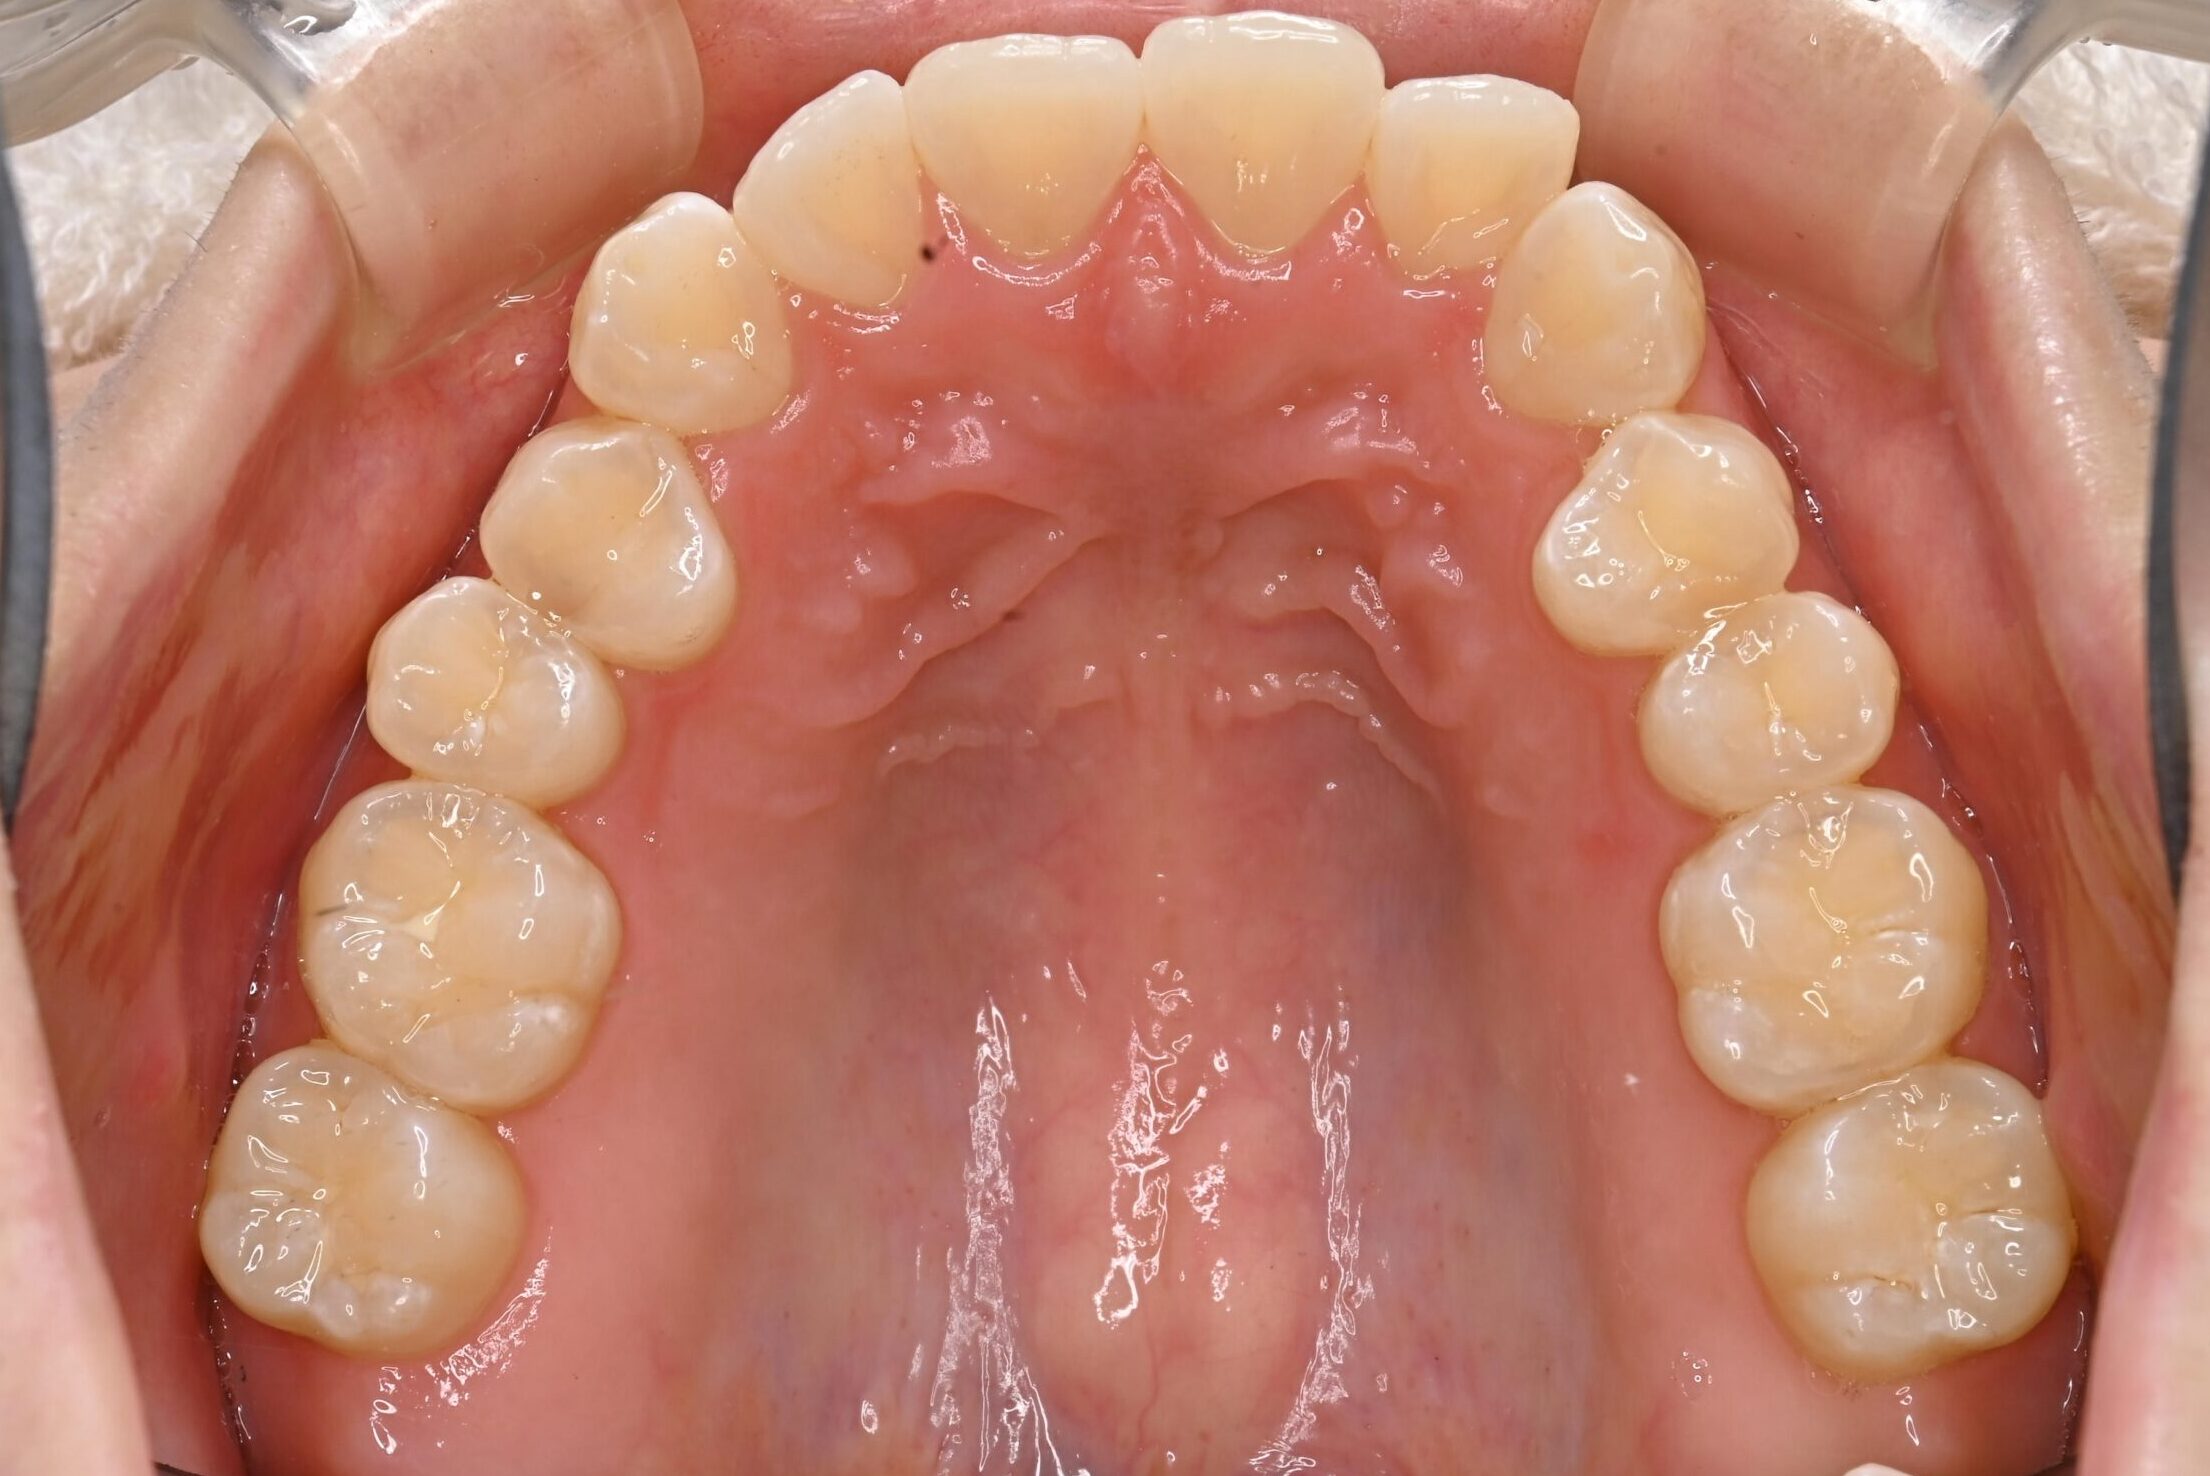

症例写真 before